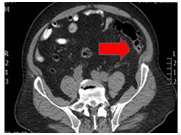

A 75-year-old male patient presents with a clinical picture of 4days of fever, LIF abdominal pain and jaundice. Clinical history was positive for a laparoscopic gallbladder removal. The patient had a BP of 85/60mmHg, HR of 91bpm, RR of 22rpm, temperature of 38.2, jaundice without peritoneal irritation. Significant lab findings included thrombocytopenia of 82.000, Creatinine of 2.62, Total bilirubin of 4.3 Direct bilirubin of 3.5 indirect bilirubin of 0.8, Alkaline phosphatase of 161, normal liver enzymes, and ABGs showing metabolic acidosis. The initial proposed diagnosis was an intra-abdominal septic shock. ICU managed included Noradrenalin, IV fluids, broad-spectrum antibiotics with Meropenem and Linezolid.  Initial Contrast abdominal CT showed a sigmoidal Hinchey 1A diverticulitis (Figure 5). Abdominal ultrasound showing a normal bile duct (Figure 6). Follow-up abdominal CT showing sigmoidal Hinchey 1B diverticulitis (microperforation), left intrahepatic portal vein thrombosis (Figure 7). Bile system MRI showing a common bile duct of 7.2mm (Figure 8). Despite treatment the patient had persistent bilirubin elevation of up to 11 mg/dl and a blood culture positive for a resistant E.coli. The patient was taken to a diagnostic laparoscopy finding a sigmoid diverticulitis with a plastron of pericolic fat tissue. A laparotomy incision was performed finding significant venous thrombosis of the left colic vein and sigmoid vein requiring a left colectomy with a Hartmann colostomy. Pathology report confirmed venous thrombosis. The patient had full recovery with antibiotics and was discharged.

Figure 7 Hinchey 1B sigmoid diverticulitis (microperforation) and left intrahepatic portal vein thrombosis.